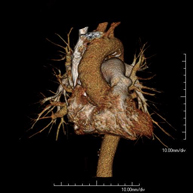

L'Angio TC cardíac o la coronariografia no invasiva és una prova diagnòstica que consisteix en l'estudi de les artèries del cor o artèries coronàries mitjançant l'ús d'un equip de TC Multidetector d'última generació (64 corones o files de detectors) i de contrast iodat amb l'obtenció d'imatges bi i tridimensionals. El TC Multidetector 64 o TCMD64 permet una adquisició d'imatges tan ràpida que es poden valorar les artèries coronàries amb alta precisió anatòmica (estrenyiments o estenosis, calcificacions, variants anatòmiques, etc.), ja que, gràcies a la seva rapidesa, evita les falses imatges que provoca el moviment constant del cor (triga menys de deu segons en adquirir unes 1000 imatges). La informació obtinguda d'un tractament en estacions de treball amb programes especialitzats en la reconstrucció de les artèries coronàries que permeten valorar el nombre, la localització i les característiques de les lesions. Tota aquesta informació s'obté de manera no invasiva: només es necessita la punció d'una vena perifèrica (en el braç). És necessari que la freqüència cardíaca no superi els 75 batecs per minut, per això els pacients han de realitzar un tractament previ amb un fàrmac betabloquejant. - Angio TC d'aorta abdominal

Prova diagnòstica no invasiva que consisteix en l'estudi de l'artèria aorta abdominal amb l'obtenció d'imatges d'alta definició anatòmica mitjançant l'ús d'un equip de TC (Tomografia Computaritzada) i contrast iodat. La qualitat de les imatges permet realitzar reconstruccions en 2D i 3D gràcies a estacions de treball especialitzades en l'estudi arterial. Està indicat en aquells pacients que pateixen malaltia vascular (arteriosclerosi), aneurismes d'aorta, en pacient amb dolor abdominal d'un possible origen vascular, en estudis prequirúrgics de lesions adjacents a l'aorta abdominal com el "mapa" vascular, etc. La informació obtinguda de forma no invasiva és indispensable per als pacients que requereixen tractament percutani o quirúrgic. En aquells pacients que només requereixen un seguiment de les lesions vasculars, aquesta tècnica és la tècnica no invasiva d'elecció juntament amb l'angio RM. - Angio TC d'artèries renals